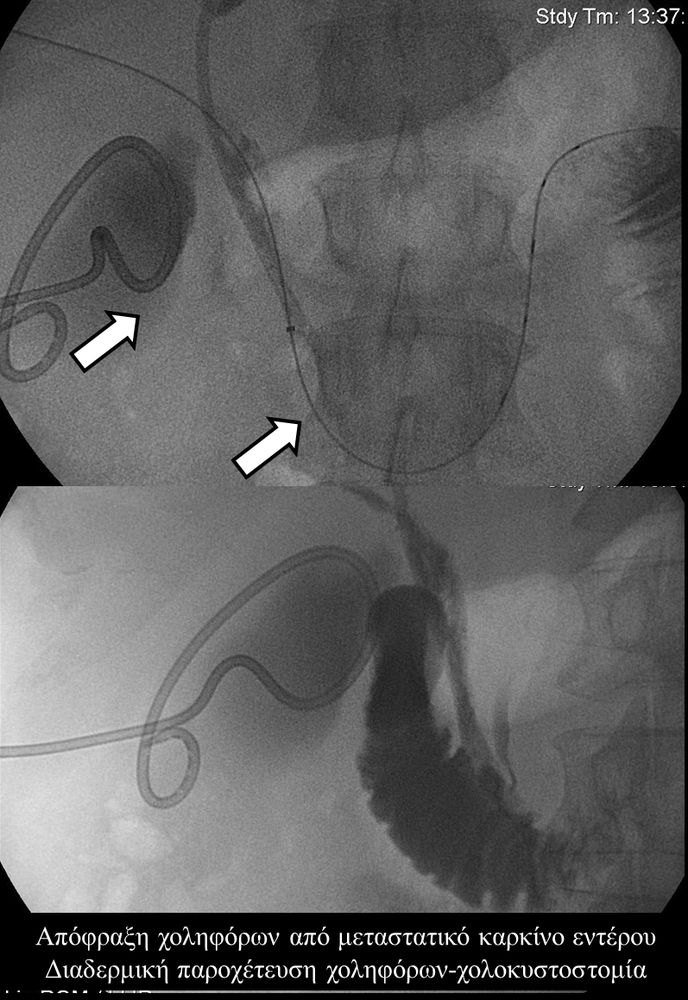

Σε πολλές περιπτώσεις πρωτοπαθών ή δευτεροπαθών όγκων ήπατος - παγκρέατος προκαλείται απόφραξη των χολαγγείων με συνοδό αποφρακτικό ίκτερο.Ο ασθενής με αποφρακτικό ίκτερο δεν μπορεί να υποβληθεί σε χημειοθεραπεία, αν δεν αποκατασταθεί ο ίκτερος με παροχέτευση των χοληφόρων.

Η παροχέτευση των χοληφόρων σε αυτές τις περιπτώσεις θα πρέπει να γίνεται άμεσα, είτε ταυτόχρονα προς τα έξω και προς το 12κτυλο (έσω-έξω παροχέτευση), είτε μόνο προς τα έξω με τη βοήθεια pigtailκαθετήρα (εξωτερική παροχέτευση)